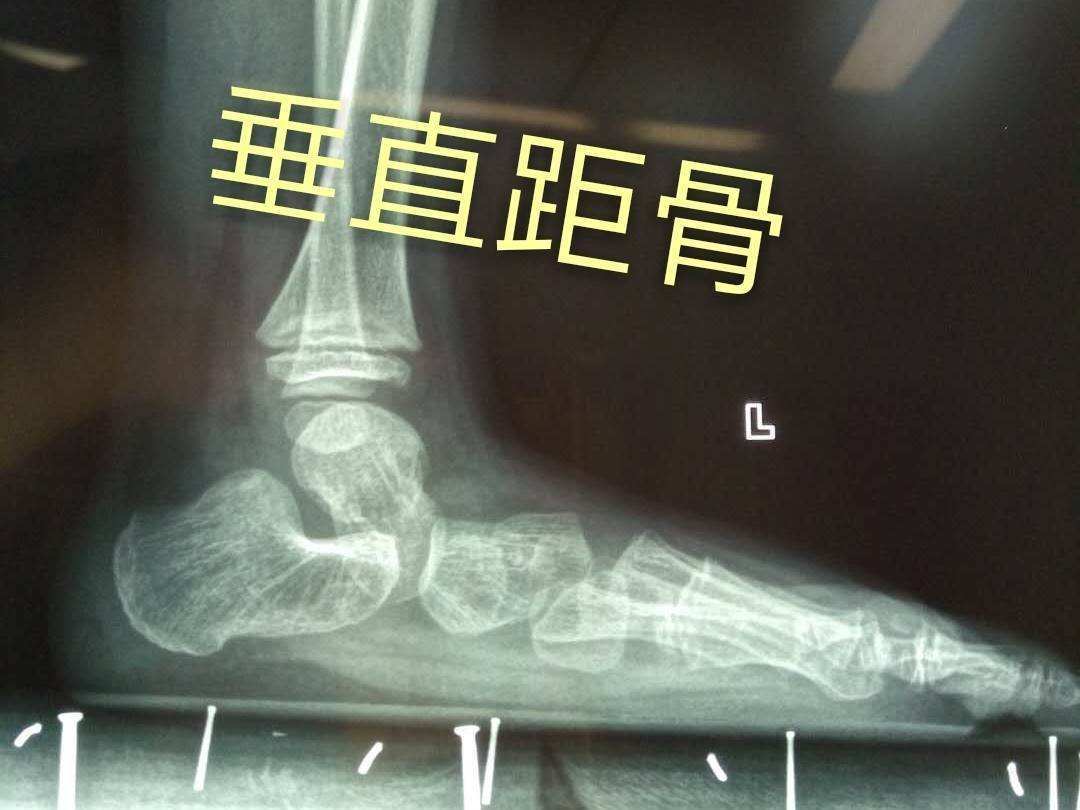

先天性垂直距骨是什么疾病治疗难度大吗